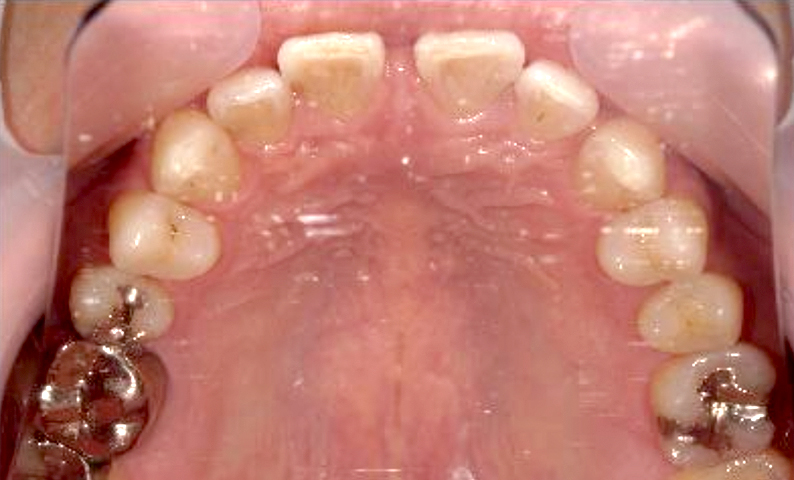

| 治療前 | 治療後 |

|---|---|

|